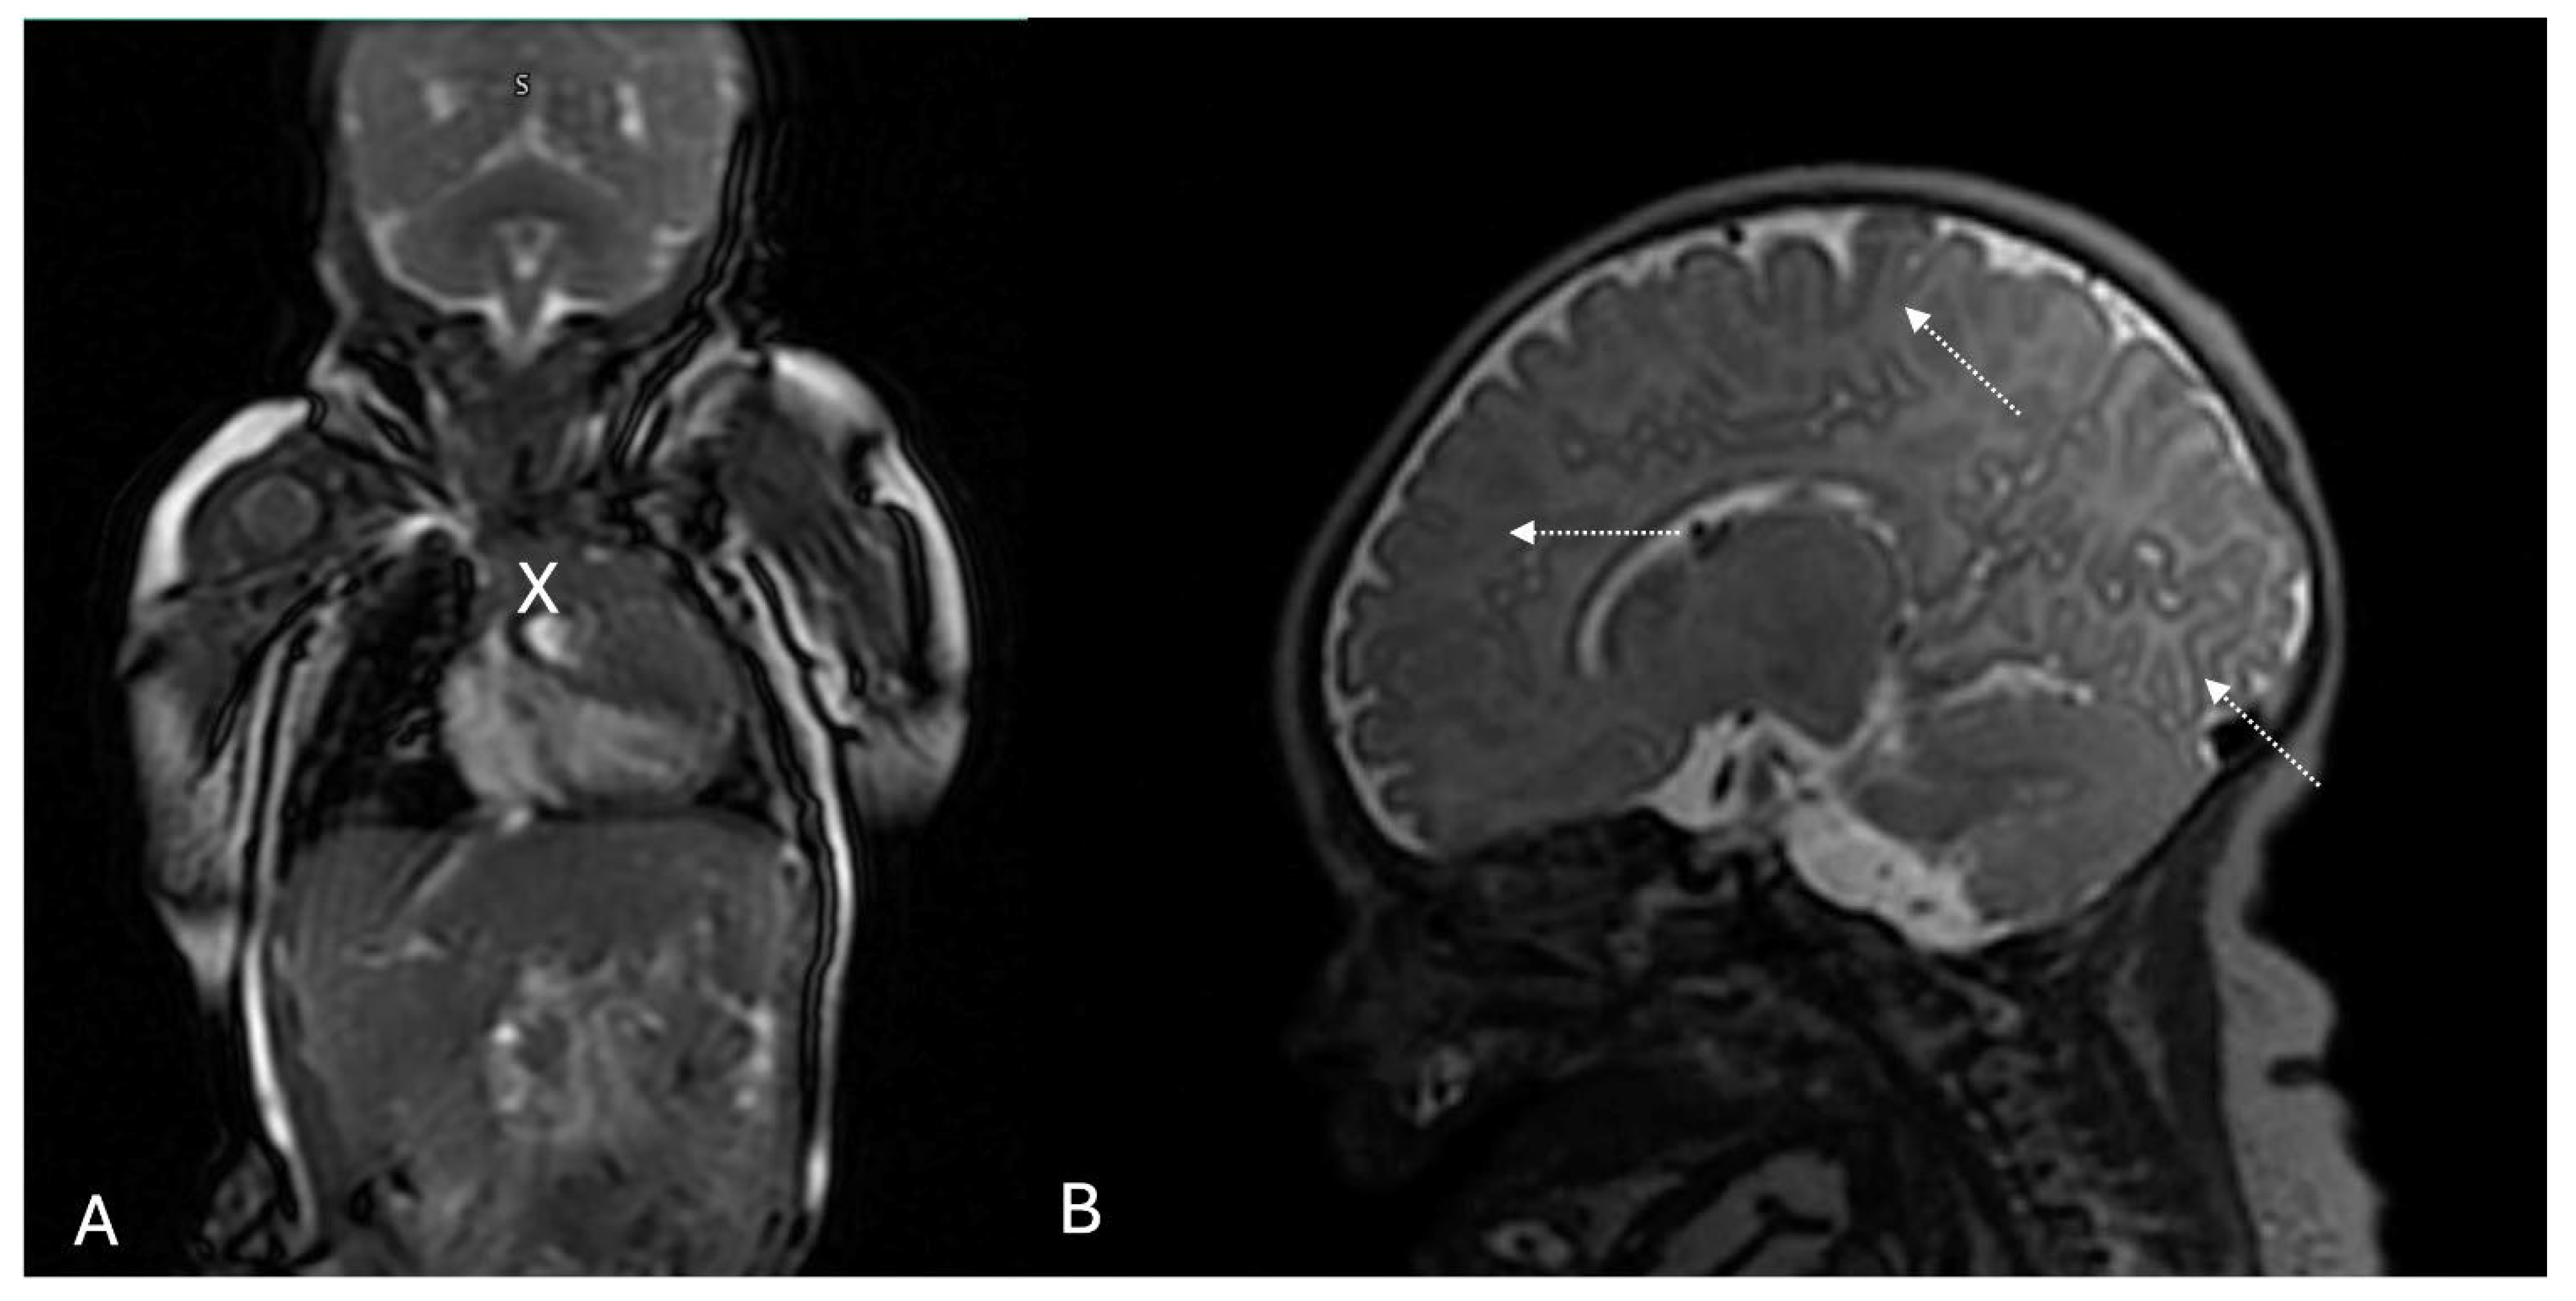

2. Case